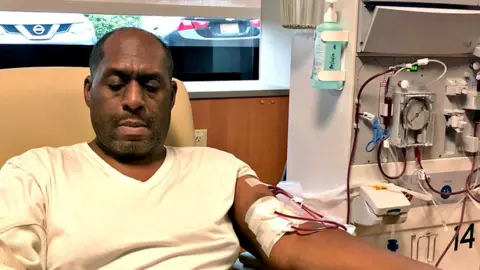

BBCTime is not on Duane Oates’ side. His body is being slowly poisoned.

Three years ago he found out that his kidneys had begun to shut down. Now, most days the 56-year-old spends hours hooked up to a dialysis machine that removes excess fluid and waste building up inside him.

Although doctors refer to dialysis as “kidney replacement therapy”, it is a stopgap at best. The machine does only 15% of the job of a normal kidney. “What’s going on with the other 85% [kidney functions] I’m not getting?” Oates asks, sitting in a medical recliner at a clinic near Washington DC. “Every day that I’m on dialysis my body is getting less healthy.”

Even for someone who is still relatively healthy like Oates, dialysis carries a heavy toll. He used to work as a project manager in the construction industry. Although he tries to keep active, having your blood filtered four mornings a week makes it impossible to hold down a job.

“When you first get hit with it, you’re kind of in a dark place. But you’ve got to fight through it and not allow it to take over you.”

Dialysis does not have to be done in a clinic. Many patients are given machines that allow them to dialyse more efficiently from the comfort of their homes. But despite Ms Maker’s friendly nagging, Oates does not feel quite ready for self-care, which requires sticking thick needles into his veins.